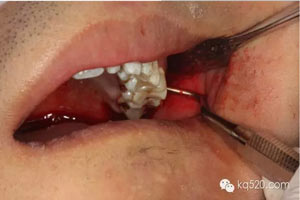

圖1.術(shù)前口內(nèi)像:上頜結(jié)節(jié)后份有一溢膿的瘺道,看不到28。

圖7.翻瓣、去骨、暴露28。

圖8.去骨后,可見(jiàn)28的牙冠,牙冠合面朝向遠(yuǎn)中水平。

徹底暴露28的牙冠和牙根。